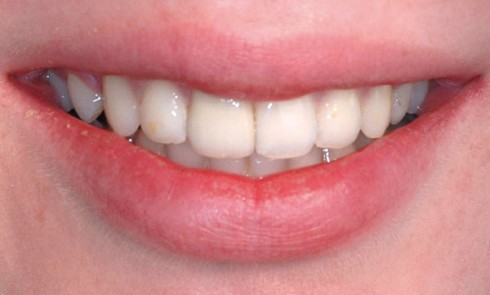

Article réservé à nos abonnés Parodontite sévère : quand l’orthodontie et les traitements biomimétiques redonnent le sourire

Les maladies parodontales entraînent des destructions irréversibles des tissus muqueux et osseux, qui peuvent avoir d’importantes répercussions esthétiques et altérer...